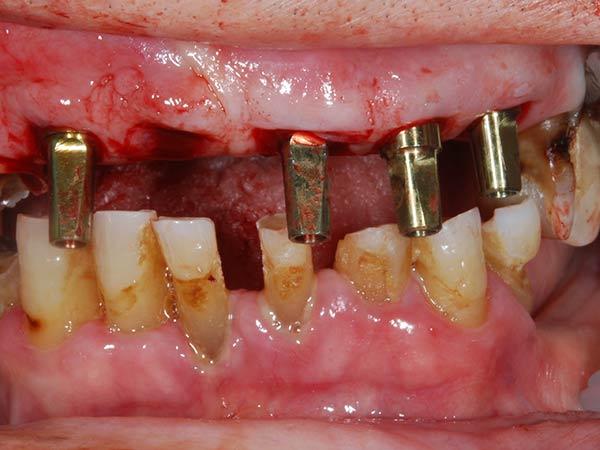

Con protesi fissa superiore e protesi fissa inferiore

I denti irrecuperabili dell'arcata superiore ed inferiore del paziente di anni 65 sono stati sostituiti da 10 impianti, cioè protesi radicolari endo-ossee che sostengono le protesi fisse superiore ed inferiore.